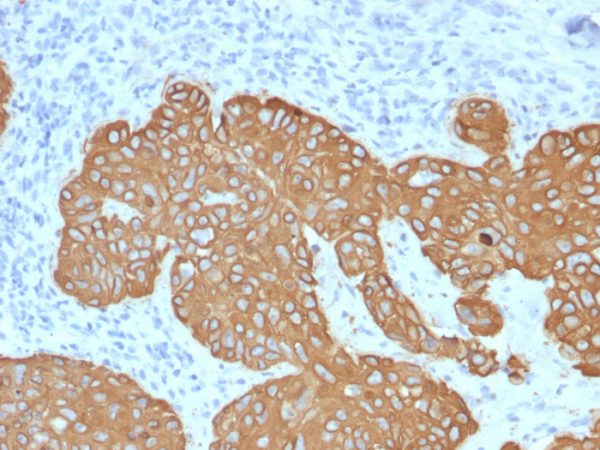

This MAb recognizes a protein of 58kDa, which is identified as Cytokeratin 5 (KRT5). This type II cytokeratin is specifically expressed in the basal layer of the epidermis with family member KRT14. Antibodies to KRT5 identify basal cells of squamous and glandular epithelia, myoepithelia, and mesothelium.Anti-cytokeratin 5 has been reported useful in the differential diagnosis of metastatic carcinoma in the pleura versus epithelioid mesothelioma. Almost all squamous cell carcinomas, half of transitional carcinomas, and many undifferentiated large cell carcinomas express.Anti-KRT5, along with anti-p63, affords a high sensitivity and specificity for squamous differentiation. Myoepithelial cells of the breast, glandular epithelia, and basal cells of the prostate are labeled with anti-KRT5.

Human esophagus, tonsil, cervix, bladder, basal cell or squamous cell carcinoma. MCF-7 or HeLa cells.